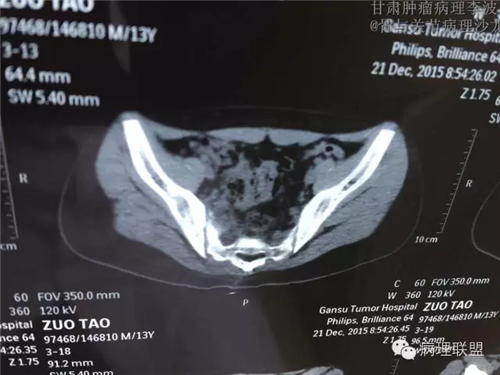

M/14 骶骨骨肉瘤-张惠箴讲解

病例由甘肃肿瘤病理 李波 提供,致谢。